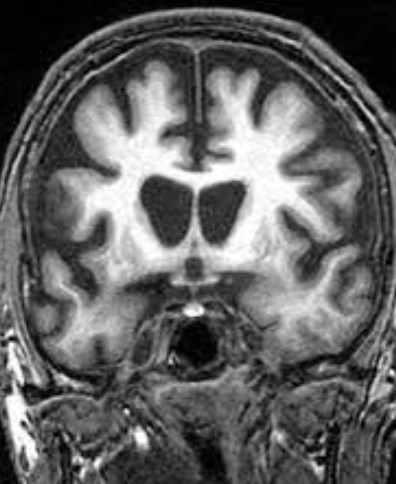

헌팅턴병은 신경계에 치명적인 영향을 미치는 퇴행성 유전 질환으로, 4번 염색체의 변이로 인해 발생하며, 주로 30~40세 사이에 증상이 나타나기 시작합니다.

헌팅턴병은 중추신경계에 영향을 미치는 유전적 퇴행성 질환입니다. 이 병은 주로 중년기에 증상이 시작되며 신체 운동, 인지 능력, 정서에 광범위하고 심각한 영향을 미칩니다.

헌팅턴병은 HTT 유전자의 변이로 인해 발생하는데 이 유전자 변이는 염색체 4의 단완에 위치하며, 특히 CAG(시토신-아데닌-구아닌) 염기서열이 정상적인 범위를 넘어서 반복되면서 발생합니다.

정상적인 사람에서는 CAG 반복이 10-35회 사이지만, 헌팅턴병 환자에서는 36회 이상, 때로는 수백 회에 이르기도 합니다.

이러한 과도한 반복은 비정상적인 헌팅틴 단백질을 생성하며, 이 단백질은 뇌의 특정 신경세포에 손상을 입혀 점차적으로 죽음을 초래합니다.